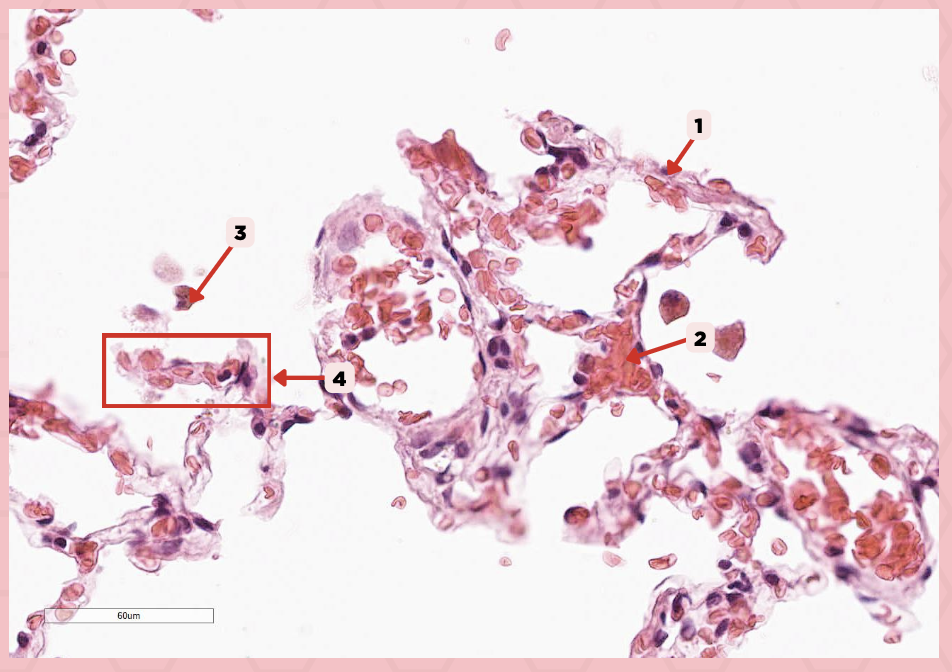

Type 1 and Type 2 Alveolar Cells

What are the 2 cell types for alveoli?

Simple squamous epithelium

What kind of epithelium are these alveolar cells?

Interalveolar septum

Identify the structure labeled as 1.

Type I alveolar cell

Identify the structure labeled as 2.

Type II alveolar cell

Identify the structure labeled as 3.

Pulmonary Alveolar Macrophages (Dust Cells)

Identify the structure labeled as 4.

Pulmonary Alveolar Macrophages (Dust Cells)

What are the most numerous cells inside the alveoli?

Pneumocyte Type I

Which of the following labeled structures covers 95% of the alveolar surface?

Type I alveolar cell

Identify the structure labeled as 1.

Type II alveolar cell

Identify the structure labeled as 2.

Pulmonary Alveolar Macrophages (Dust Cells)

Identify the structure labeled as 3.

Endothelial Cells

Identify the structure labeled as 4.